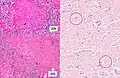

A case of miliary tuberculosis in an 82-year-old woman:

Histopathology, showing epithelioid granulomas with multinucleated giant cells and acid-fast bacilli